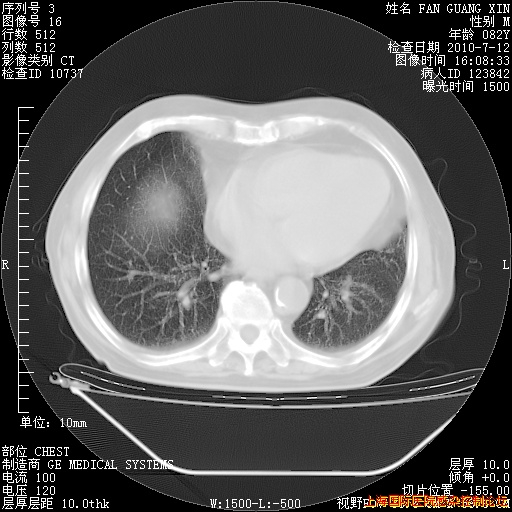

补发6月12日肺部CT肺窗

6月12日肺窗

整整相隔30天的肺部CT好像有所好转啊。甲强龙减量第3天,需要观察体温。